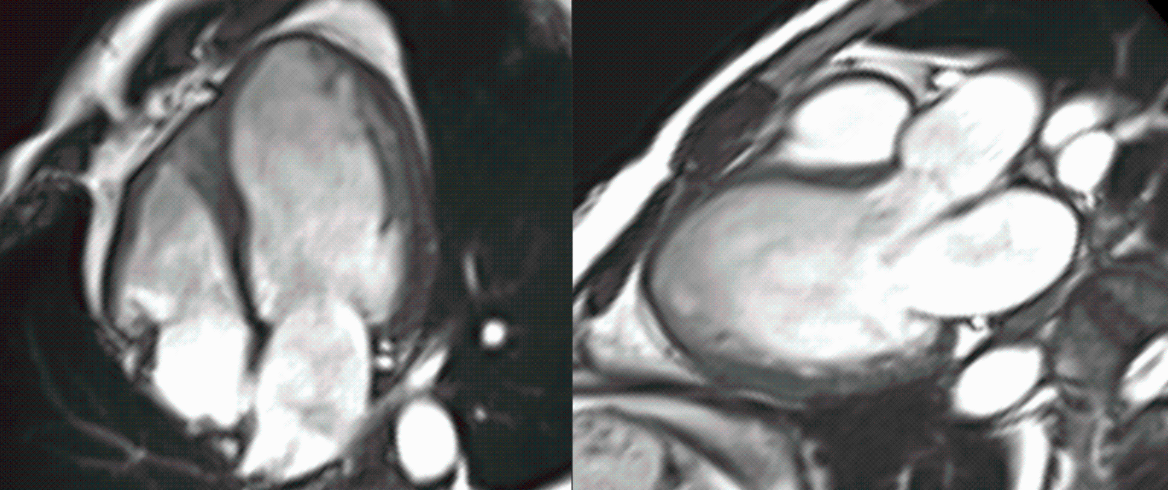

Conundrum of Ischemic DCM